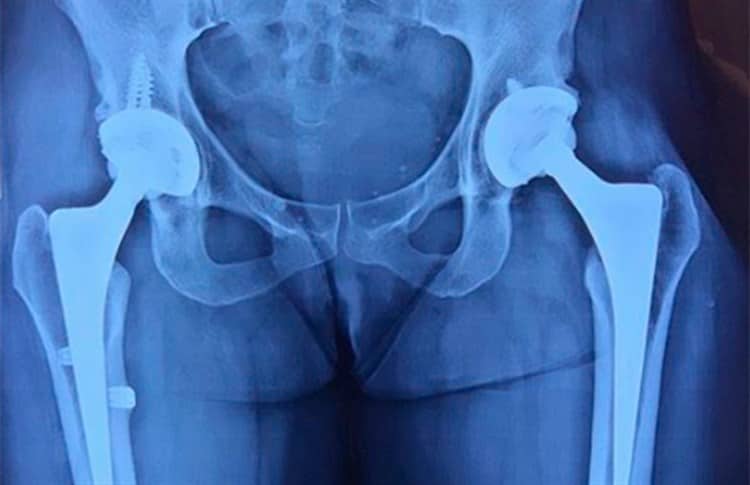

Alejandra Guzmán compartió en su cuenta de Instagram la fotografía de una placa que revela las prótesis que usa en la cadera.

La cantante de 51 años escribió junto a la reveladora imagen: "Soy de titanio".

Para enero de 2013 se somete a cirugía de cadera para colocarle una prótesis. "La podemos reconstruir, será La Guzmán biónica", escribe en Twitter. El desgaste en su cadera tiene que ver con sus años de bailarina.

A partir de entonces Alejandra tuvo que regresar al quirófano en múltiples ocasiones; en noviembre de 2016 vuelve una vez más al quirófano para su intervención número 22. Le colocan la segunda prótesis de titanio en la cadera.